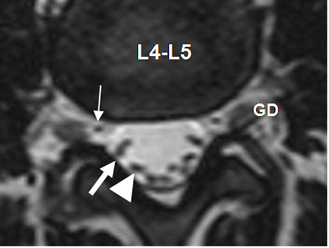

Fig 27. Cola de caballo.

RM axial en T2. Distribución normal de las raíces de la cola de caballo. Cada raíz va ascendiendo, para salir por su respectivo agujero de conjunción. Espacio L4-L5. Sale la raíz de L4. (Flecha delgada). Posteriormente se localiza la raíz de L5 (Flecha gruesa) y por detrás S1. (Punta de flecha). GD: ganglio de la raíz dorsal.